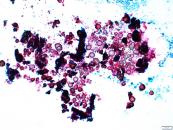

第37回日本臨床細胞学会九州連合会学会(佐賀)スライドカンファレンス症例1

種別:呼吸器

出題:○古賀 裕1、山本 将義2、藤本 翔大2.1国立病院機構 九州がんセンター 病理診断科、2国立病院機構 九州がんセンター 臨床検査科

| 年齢 | 60歳代 | 性別 | 男性 |

|---|---|---|---|

| 採取部位 | 肺腫瘍 | 採取方法 | 捺印 |

| 検体処理法 |

臨床所見

既往歴:59歳 前立腺癌に対してホルモン治療、放射線治療、59歳高血圧、63歳糖尿病で内服加療中

現病歴:前立腺癌の経過観察のCTにて右肺結節を指摘された。PSA含めて腫瘍マーカーは正常であった。本標本は術中迅速組織診断用に提出された肺腫瘍の捺印細胞診検体である。

| 正解 | 5.転移性肺腫瘍(前立腺癌) |

|---|

▼選択肢及び投票結果

| 1.類基底細胞型扁平上皮癌 | 9件 | (11.2%) | |

| 2.大細胞神経内分泌癌 | 5件 | (6.2%) | |

| 3.腸型腺癌 | 42件 | (52.5%) | |

| 4.転移性肺腫瘍(大腸癌) | 14件 | (17.5%) | |

| 5.転移性肺腫瘍(前立腺癌) | 10件 | (12.5%) | |

| 投票総数 | 80件 | (100%) |